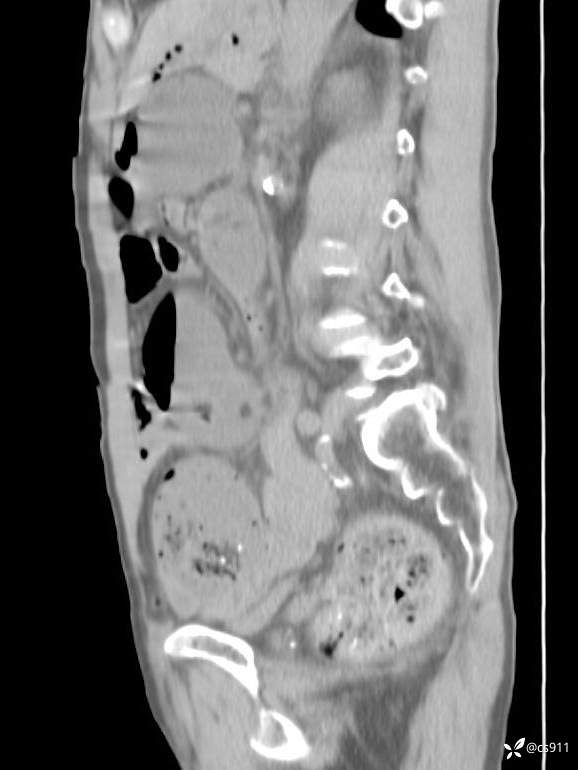

急腹症之急诊CT,原因?答案公布

男,77岁,腹痛、腹胀伴恶心呕吐1天。呕吐胃内容物,非喷射性呕吐,有咖啡色样胃内容物,诉有胃穿孔病史。查体:全腹平,下腹部压痛,全腹无反跳痛,叩诊呈浊音,移动性浊音阴性,肠鸣音减弱,1-2次/分。肛检:直肠未扪及明显肿物,可触及大量粪块。

血淀粉酶(AMY) HH 1859 U/L 35-135